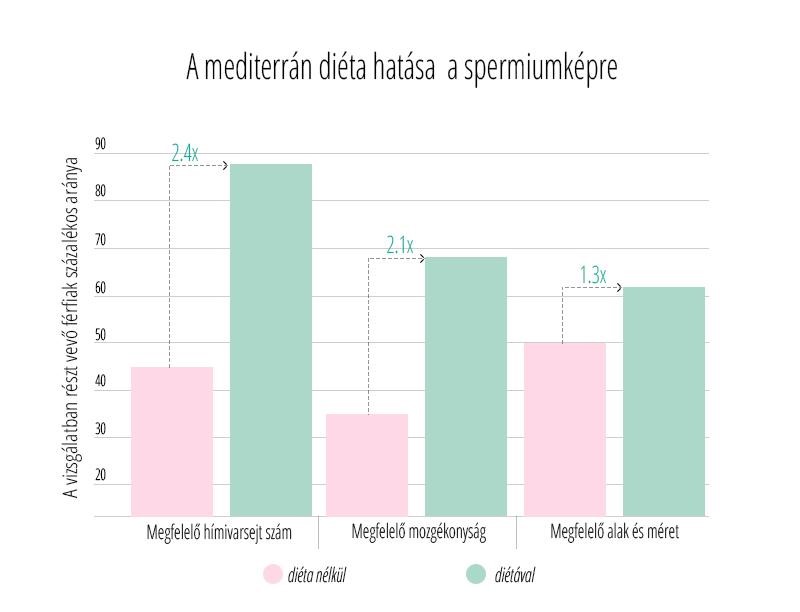

Az edukáció olyan fontos kérdéseket érint, mint: mi számít meddőségnek, mikor érdemes szakemberhez fordulni, hogyan hat az életkor a termékenységre, illetve milyen kockázatot jelentenek a szexuális úton terjedő fertőzések. Az iránymutatás külön kitér a legfontosabb kockázati tényezőkre, mint a dohányzás, a túlzott alkoholfogyasztás, az elhízás vagy éppen az alultápláltság, melyek mind kedvezőtlenül hathatnak a reproduktív egészségre. Ezzel szemben a kiegyensúlyozott, tápanyagokban gazdag étrend, a rendszeres testmozgás, valamint a dohányzás elhagyása bizonyítottan hozzájárulhat a termékenység megőrzéséhez és a későbbi problémák megelőzéséhez.